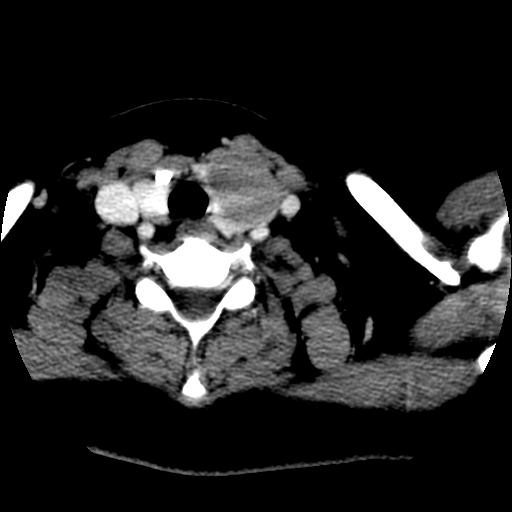

标题: CT25491:女,55岁,发现左侧甲状腺肿块一个月。 [打印本页]

标题: CT25491:女,55岁,发现左侧甲状腺肿块一个月。

女,55岁,发现左侧甲状腺肿块一个月,彩超示:甲状腺多发结节伴左叶结节液化。

左右叶都有,峡部也受累,有钙化,考虑结甲可能性大。

考虑左侧甲状腺结节性甲状腺肿,不排除甲状腺腺瘤。